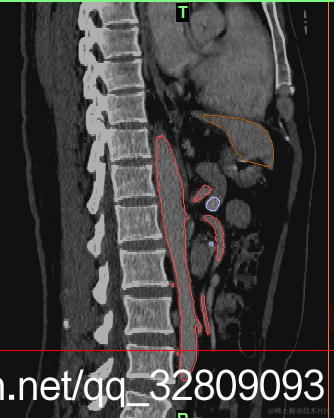

正面图(肝脏+动脉+门静脉+腔静脉)                                反面图                                                          透视图

三种视图: